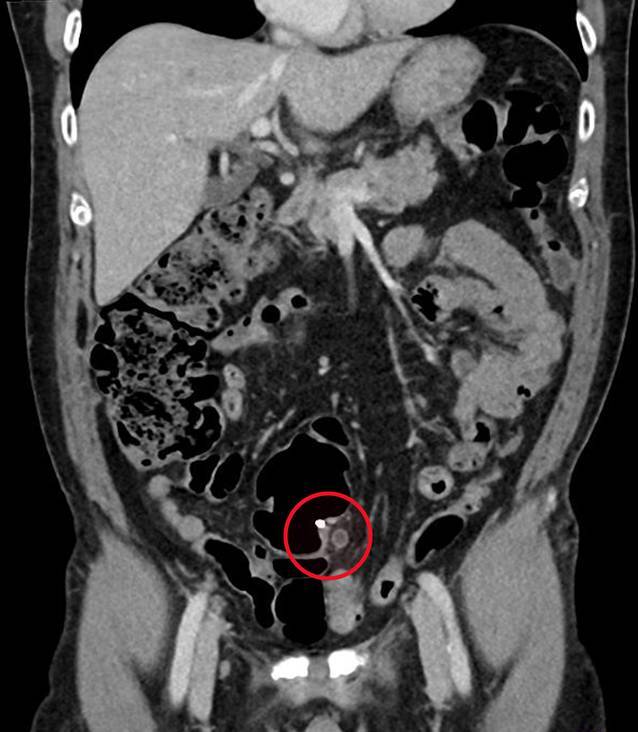

Nach stationärer Aufnahme zur weiteren Abklärung wurde eine Kontrastmittel-CT des Abdomens durchgeführt, welche die Hydronephrose Grad III links auf eine Obstruktion durch den Endoskopieclip zurückführte (Abb. 1). In einer Akutkolonoskopie wurde der Mainz-Pouch II als normal befundet, jedoch konnten die Ureterenmündungen beidseits – bis dato in den jährlichen Nachsorgekolonoskopien im intramuralen Bereich unauffällig – nicht dargestellt werden. Es zeigten sich lediglich zwei fibrinbedeckte Polypenabtragungsstellen (Abb. 2). In Zusammenschau der Befunde waren die Ureterenmündungen im Pouch als vermeintliche Polypen abgetragen, verödet und geclippt worden. Der in der CT beschriebene Clip war zwischenzeitlich offenbar abgegangen.